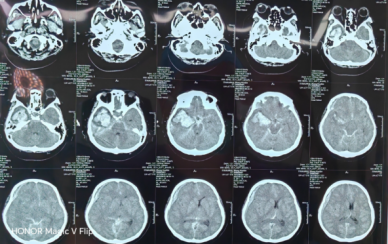

生死时速!多学科联动上演脑卒中急救“教科书式”操作5月,一位急性脑卒中患者生命垂危,120急救站闻令而动,医院院前急救无缝衔接,急诊-影像-检验高效联动,15分钟完成诊断闭环。多学科团队直通导管室,到院后用时不到1小时,成功为斑块致脑血管慢性堵塞患者恢复脑部血流。

清血肿•准夹闭•挽生命•助健康 济南南郊医院一体化救治脑动脉瘤破裂并发脑疝危重患者9月,一位动脉瘤破裂并发脑疝危重患者到院就医。患者到院时已处于深度昏迷状态,呼吸、心跳等生命体征极不平稳,随时可能停止。检查发现,其脑动脉瘤破裂后出血量巨大,形成典型脑疝表现,死亡率极高。脑科团队争分夺秒、配合默契,快速清除压迫大脑的巨大血肿,更在视野不清、操作空间极其有限的情况下,精准完成动脉瘤夹闭。后续在脑病科医护团队的精心治疗和护理下,患者从深度昏迷中苏醒,复查脑血管造影显示动脉瘤夹闭完全!为助力患者身体机能恢复,济南南郊医院脑病科与康复科紧密合作,为患者量身定制了个性化的康复方案,通过系统训练,最大程度地促进其神经功能恢复,目前患者康复进展显著,已完成PEEK材料颅骨修补手术。手术采用先进的PEEK(聚醚醚酮)材料作为修补植入物,该材料具有影像兼容性极佳、生物相容性卓越、可进行精准个性化定制、力学性能优异等优势。不仅能恢复头颅外观,更能为脑组织提供保护,改善脑血流灌注,有助于神经功能的进一步恢复。